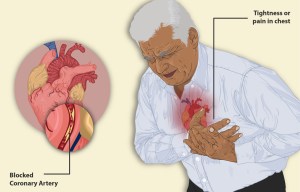

Hypertension causes inflammation and remodeling of vessels, therefore effecting and harming organs (brain, kidney, heart, eye/retina). Untreated hypertension is a major cause of strokes, heart attack, kidney disease, heart failure. Hypertension usually does not give any symptom until major organ damage.

Treatment of hypertension is important. To give an example and estimate, each 20 mmHg systolic blood pressure increase after 115 systolic blood pressure, doubles patients risk of dying from vascular disease (stroke, heart attack, kidney failure). Even 10 mmHg decrease of systolic blood pressure decreases early death by more than 10%.